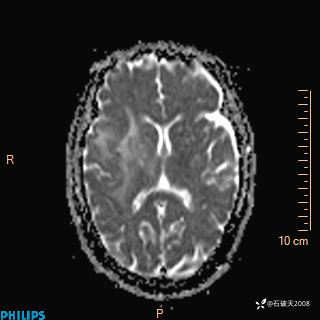

2024.2.21MR

DWI

ADC